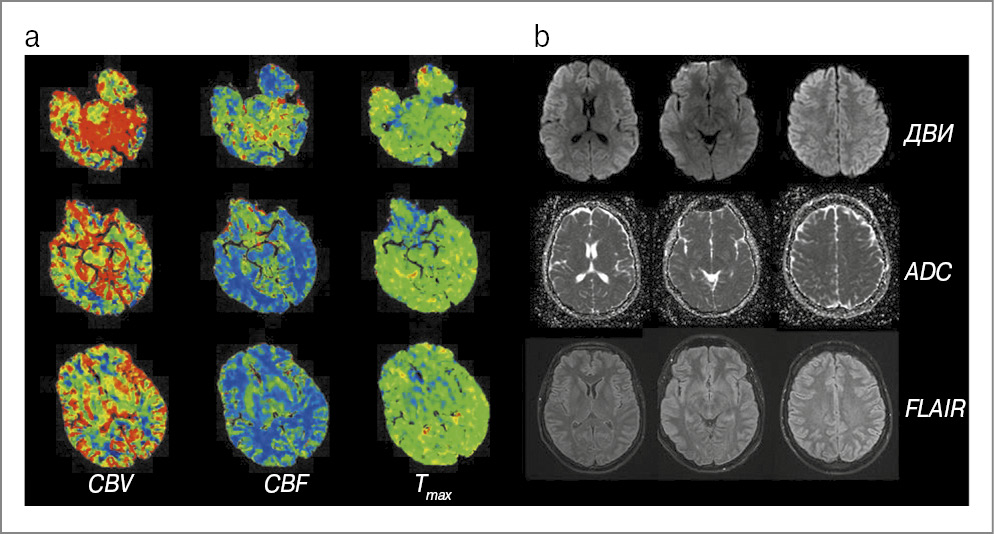

При поступлении отмечена моторная афазия, иного неврологического дефицита не обнаружено. Проведена КТ ГМ, зон патологической плотности не выявлено. Признаки окклюзии крупных и средних артерий, а также венозного тромбоза по данным КТ-ангиографии не выявлены. По данным КТ-перфузии кровоток замедлен (удлинение показателя Tmax) в левом полушарии ГМ – в зонах, выходящих за границы артериальных бассейнов. В результате МРТ ГМ патологических изменений не выявлено (рис. 2).

Рис. 2. Клинический случай №2: a – КТ-перфузия; b, c – чреспищеводная ЭхоКГ (описание в тексте).

Клиническая и радиологическая картина расценена дежурным неврологом как «маска» инсульта, принято решение не проводить внутривенный тромболизис. На утро следующего дня у пациента сохранялась легкая афазия. В 11:00 выполнена контрольная МРТ, результат которой также оказался нормальным. Через 20 ч с момента развития симптомов речь полностью восстановилась. В рамках выяснения причины пролонгирования МА выполнена чреспищеводная эхокардиография (ЭхоКГ), выявлена аневризма межпредсердной перегородки (R-тип, глубина 12 мм) в сочетании с открытым овальным окном (ООО) диаметром 3 мм (рис. 2, b). При тугом наполнении правых камер аэрированным физиологическим раствором во время натуживания (маневр Вальсальвы) отмечался массивный сброс микропузырьков в левое предсердие (рис. 2, c). По данным дуплексного сканирования тромбов в венах нижних конечностей не обнаружено. Пациент выписан в удовлетворительном состоянии.

Второй представленный случай примечателен тем, что наличие типичного для МА анамнеза и изменений на КТ-перфузии позволило дежурному врачу принять обоснованное решение о непроведении внутривенного тромболизиса. Известно, что у 2,2% пациентов, поступающих в стационар с подозрением на инсульт, выявляется его маска в форме мигрени. В когорте пациентов, которым проведен тромболизис, данный показатель составляет 0,5% [24, 25]. На долю мигрени приходится 1 из 10 случаев всех масок инсульта [26]. В описании приступа у нашего пациента имелись типичные характеристики МА, в частности наличие «марша по сосудистым территориям» [27], однако вызывала сомнение в «безопасном диагнозе» продолжительность речевых нарушений. На наш взгляд, КТ-перфузия – надежный инструмент дифференциальной диагностики мигрени и инсульта: при МА гипоперфузия часто наблюдается в «задних» отделах мозга, выходит за границу сосудистого бассейна (может охватывать все полушарие) и имеет менее выраженное увеличение среднего времени транзита контрастного агента, чем при артериальной ишемии, с минимальным снижением объема мозгового кровотока [28].